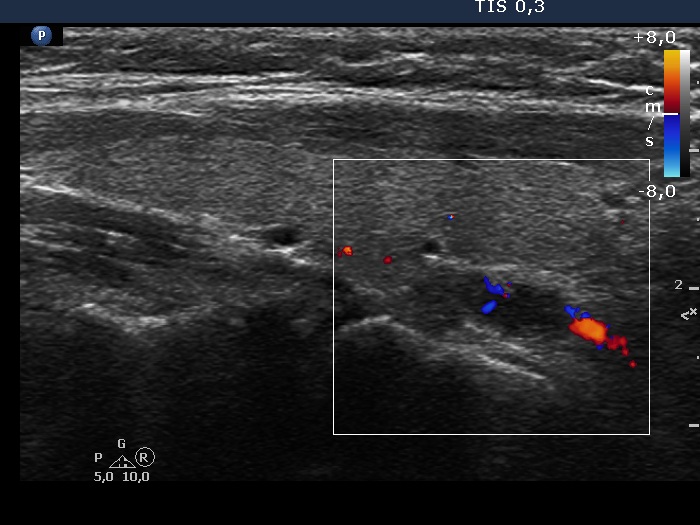

Ultrasonography. The thyroid was echonormal. There was a small cystic or deeply hypoechoic lesion in the lower-dorsal part of the right lobe. The lesion was not avascular. The left lobe has several discrete areas without any clinical or oncological significance.